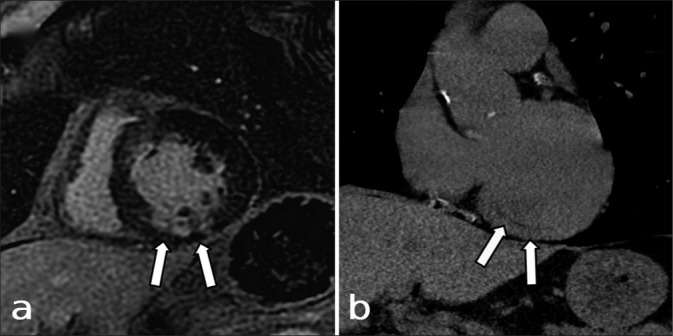

Abstract Image